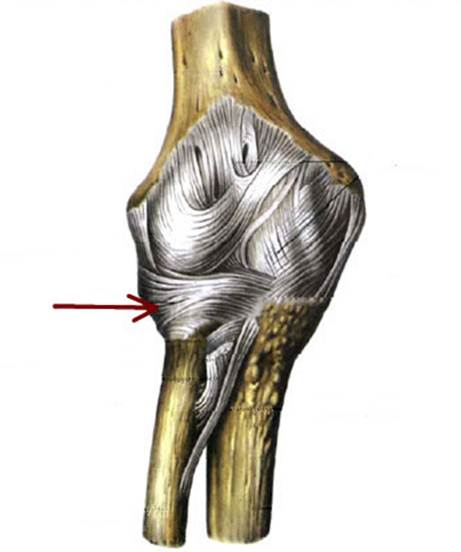

S: Стрелка указывает на lig. Collateralis ulnare

S: Стрелка указывает на lig. Anulare radii

S: Стрелка указывает на lig. Collaterale radiale

S: Стрелка указывает на membrana interossea antebrachii